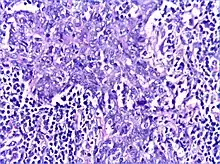

Benign lymphoepithelial lesion or Mikulicz' disease is a type of benign enlargement of the parotid and/or lacrimal glands. This pathologic state is sometimes, but not always, associated with Sjögren's syndrome.